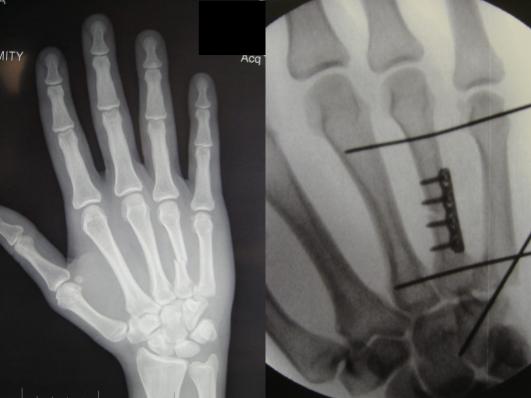

Hand Trauma B78